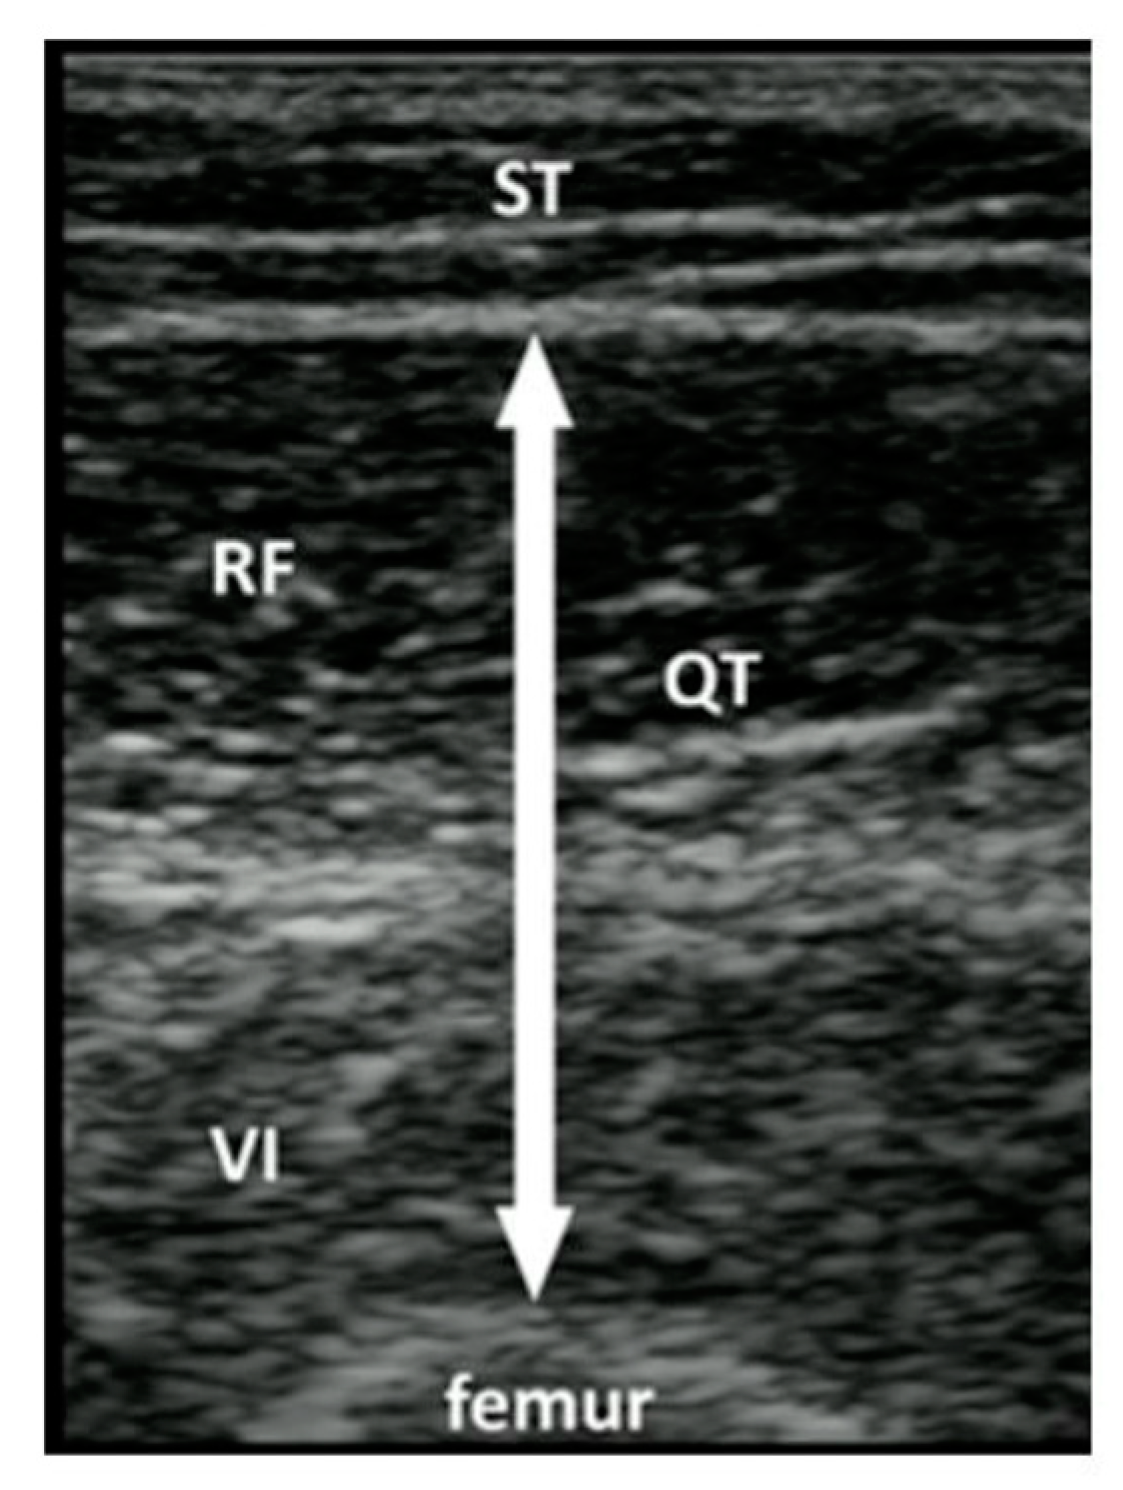

- Galindo Martín, C.A.; Monares Zepeda, E.; Lescas Méndez, O.A. Bedside Ultrasound Measurement of Rectus Femoris: A Tutorial for the Nutrition Support Clinician. J. Nutr. Metab. 2017, 2017, 2767232. [Google Scholar] [CrossRef]

- Delaney, S.; Worsley, P.; Warner, M.; Taylor, M.; Stokes, M. Assessing contractile ability of the quadriceps muscle using ultrasound imaging: Contractile Ability of Quadriceps. Muscle Nerve 2010, 42, 530–538. [Google Scholar] [CrossRef]